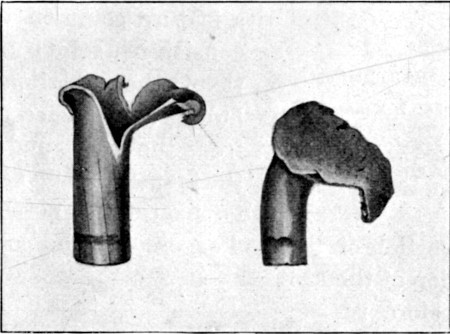

35. Apical Lee-Metford Ricochets90

36. " " " 91

37. Four Types of Soft-nosed Bullets92

38. 'Set-up' Soft-nosed Lee-Metford Bullets92

39. Flattened, Solid-based Mantle From Ricochet93

40. Mauser Bullet, Jeffreys-Tweedie Modification94